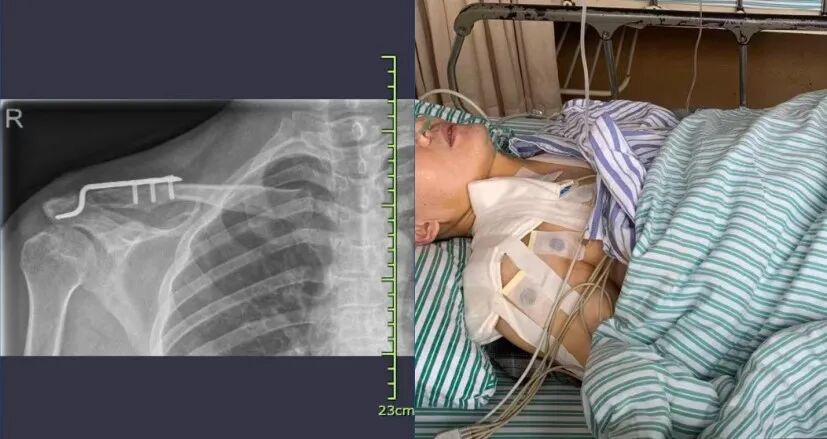

結果這幾天卻連日下起了小雨。這不王爺爺剛要出門,一不小心摔了一跤,在醫院躺了好幾天了。

護士查房的時候,見到王爺爺就說,您平時不注意曬太陽,也不注重補鈣吧!

別不把缺鈣放在心上,冬季陽光減少,加上缺少運動,不少朋友的老胳膊老腿又開始犯老毛病了……